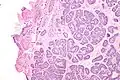

| Micrograph of a Sertoli cell nodule. H&E stain. | |

Sertoli cell nodules are unencapsulated nodules that consist of:[2][3][4]

- cells arranged in well-formed tubules (that vaguely resemble immature Sertoli cells), with

- bland hyperchromatic oval/round nuclei that are stratified, and

- may contain eosinophilic (hyaline) blob in lumen (centre).